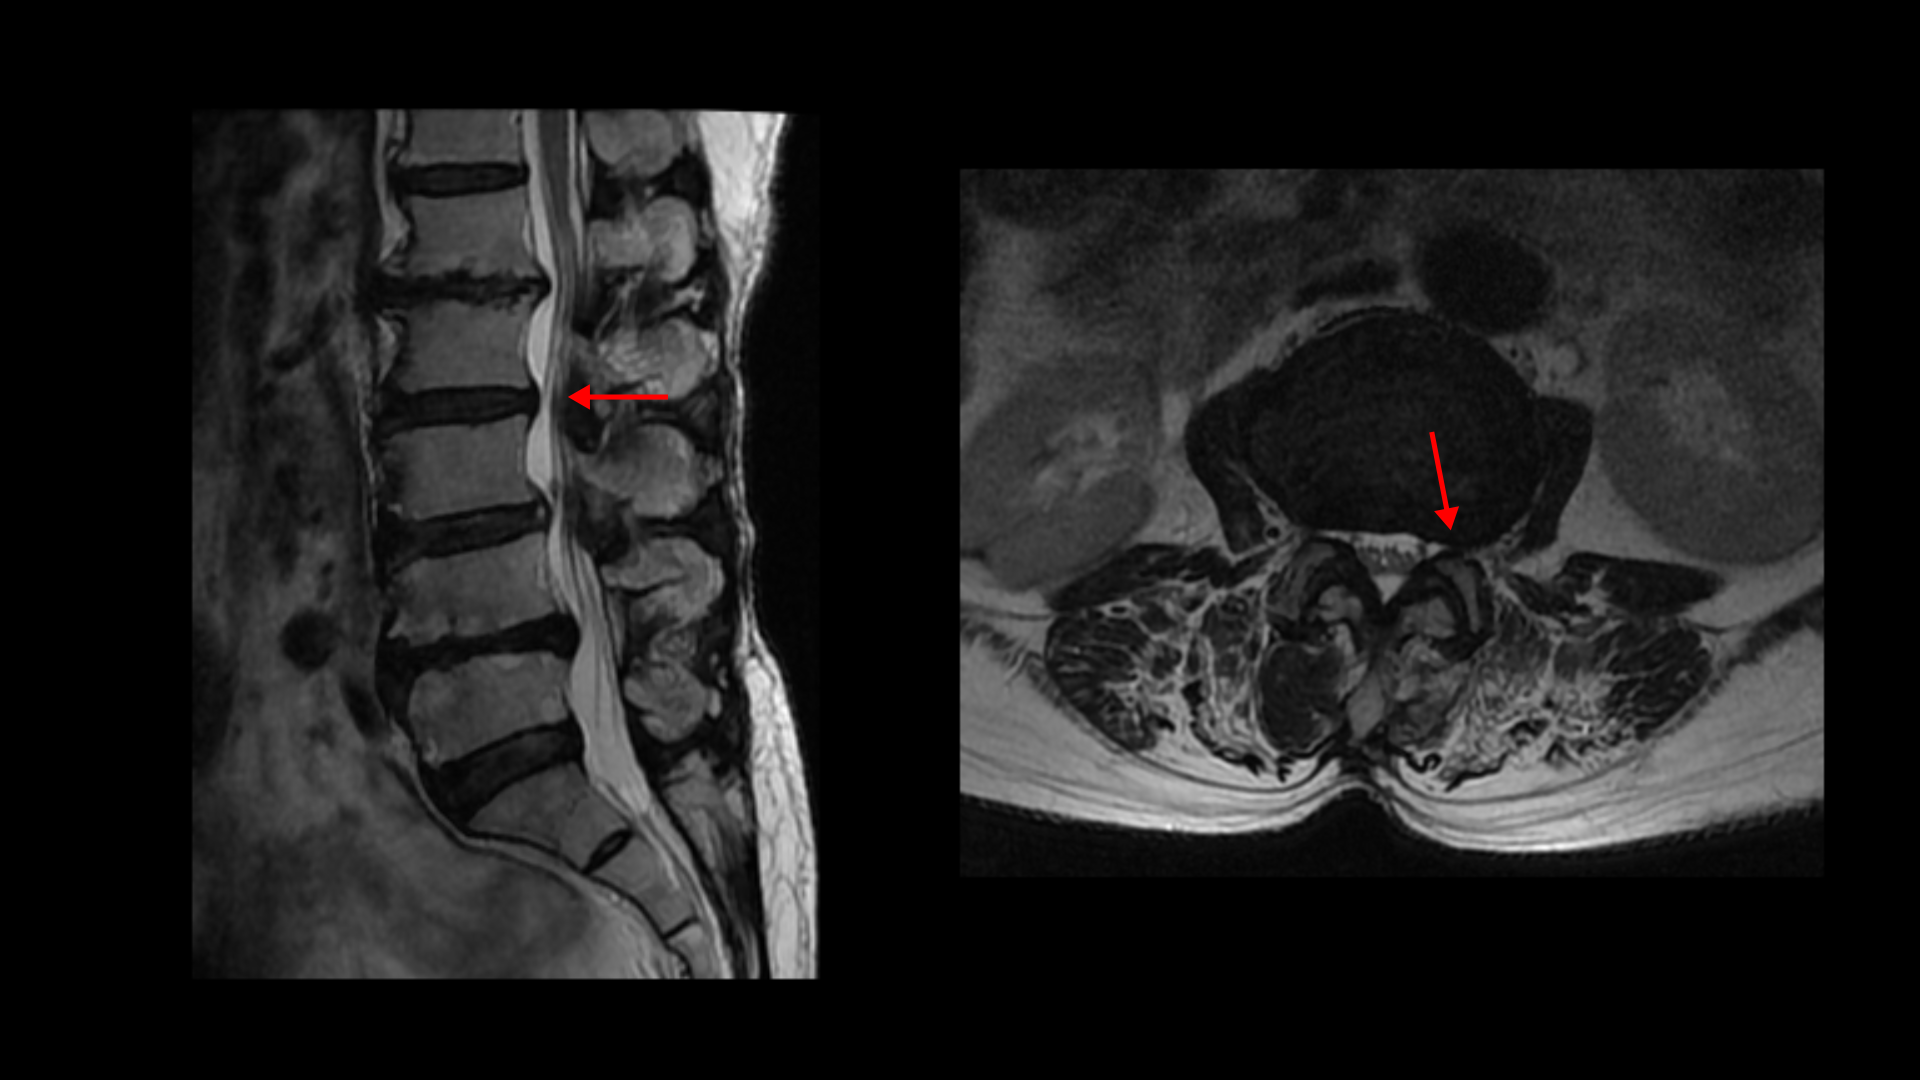

이분 MRI를 보면 허리 다섯 마디에 전부 퇴행성 디스크가 있습니다.

1-2번에는 오른쪽으로 디스크도 밀려 나와 있고 중심성 협착도 있습니다.

2-3번에는 왼쪽으로 신경구멍 쪽으로 디스크가 밀려 나와있습니다.

3-4번에는 중심성 협착이 있고

4-5번에는 왼쪽으로 디스크가 밀려 나와있고 심한 중심성 협착과 왼쪽 추간공협착도 있습니다.

5-1번에는 왼쪽으로 디스크가 밀려 나와있고 전반적으로 왼쪽이 상태가 더 안 좋은데 이분의 증상도 왼쪽 엉덩이와 다리의 통증과 저림 및 마비감입니다.